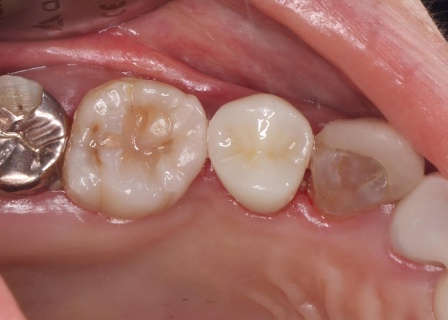

50代女性銀歯の下の虫歯を除去しセラミックで修復したケース

レントゲン像で金属の下に虫歯があり、患者さんは入れ替えを強く希望されました。

特に審美的な要求をされたため、セラミック修復の説明をし、治療の同意を得ました。